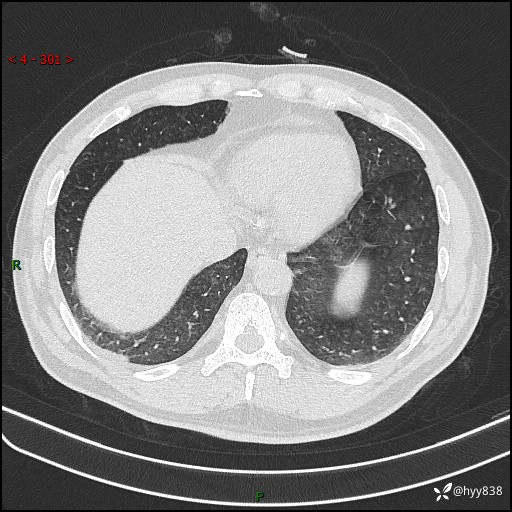

辅助检查:CT

胸部HRCT